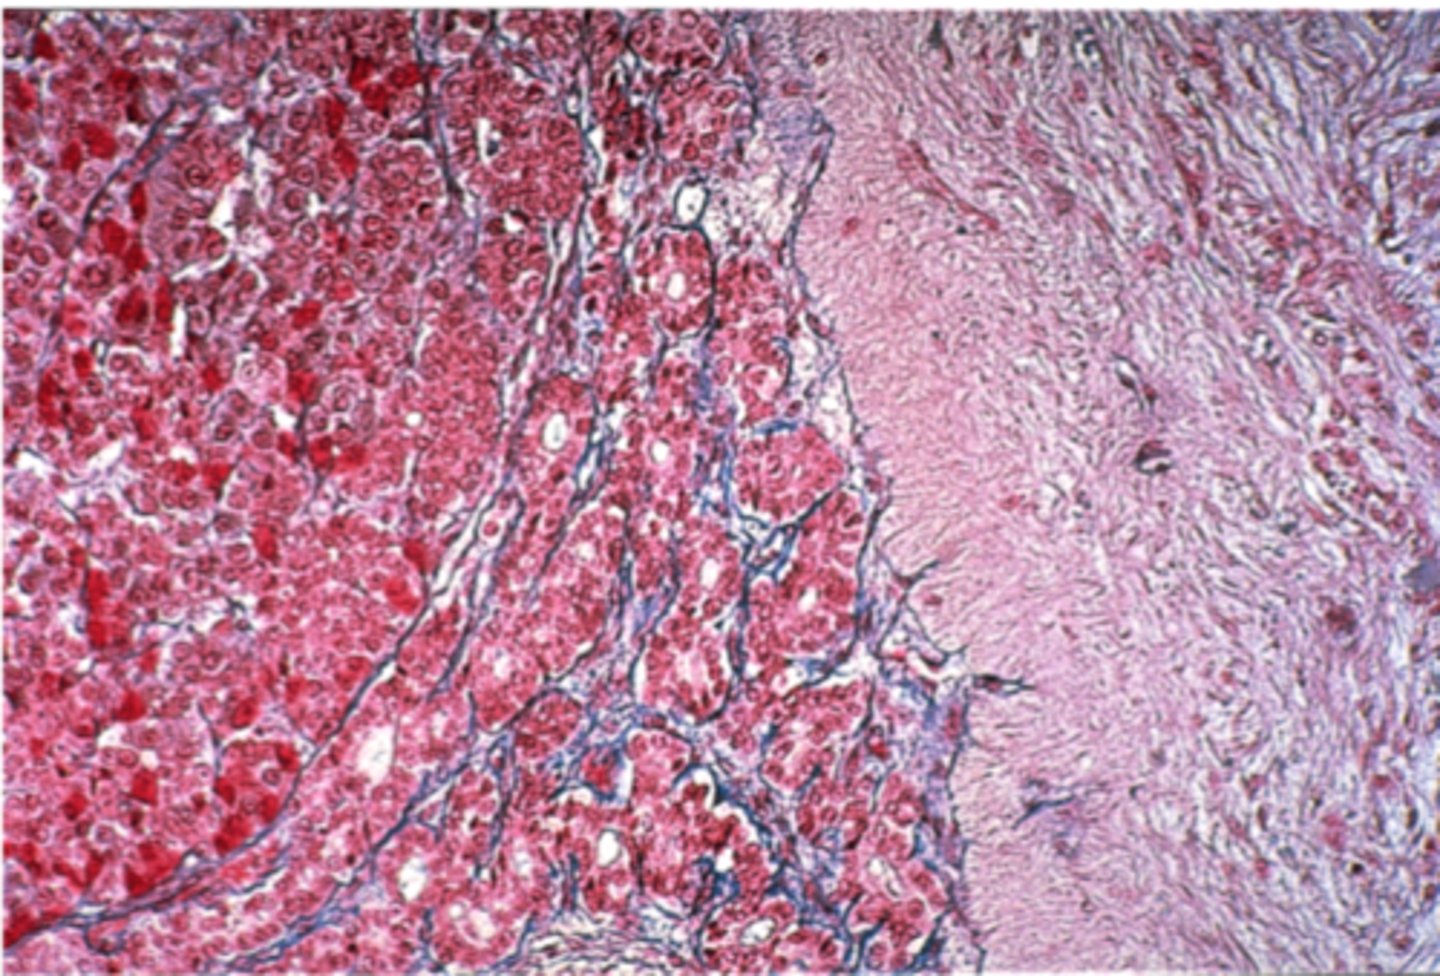

Pancreas

what is this?

insulin

What hormones does the pancreas produce?

Islets of Langerhans

what is this pointing to?

pancreas

what organ is islet of langerhans on